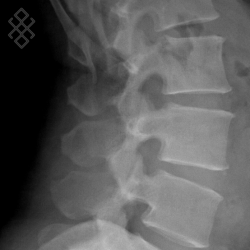

Radiographie du Rachis lombaire

La durée de l'examen est d'environ 5 minutes. Un ou plusieurs clichés radiographiques seront effectués. Le manipulateur vous positionnera en fonction de l'incidence radiologique à réaliser. Sauf indication contraire, il sera important de ne pas bouger durant la prise de clichés.